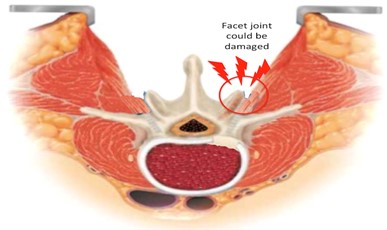

Joint: Facet joint, an important structure for maintaining both mobility and stability of spine may get damaged destabalising the spine grossly.